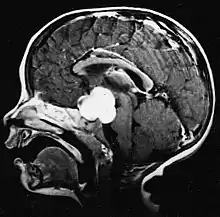

Cette tumeur est typique de la fosse postérieure, où elle est localisée dans les deux hémisphères du cervelet ou dans le vermis cérébelleux. Parce qu'il est envahissant et à croissance rapide, il se propage généralement à d'autres parties du système nerveux central (SNC) via le LCR et peut infiltrer le plancher du quatrième ventricule voisin et les méninges. Plus rarement, des métastases supplémentaires du SNC peuvent survenir. Lorsque la tumeur maligne survient, les symptômes comprennent la perte d'équilibre, l'incoordination, la diplopie, la dysarthrie et l'atteinte du quatrième ventricule, ce qui entraîne souvent une hydrocéphalie obstructive, des maux de tête, des nausées et des vomissements et une démarche instable.

L'IRM montre généralement une lésion de contraste massive impliquant le cervelet. Comme mentionné ci-dessus, le médulloblastome a une forte propension à infiltrer localement les leptoméninges ainsi qu'à se propager à travers l'espace sous-arachnoïdien, impliquant les ventricules, la convexité cérébrale et les surfaces leptoméningées de la colonne vertébrale. Par conséquent, il est nécessaire de mettre en résonance tout l'axe crânio-spinal.

Le but de la chirurgie est d'enlever autant que possible la masse présentée par la lésion. En effet, les tumeurs résiduelles postopératoires entraînent un moins bon pronostic. La présence de cellules tumorales dans le liquide céphalo-rachidien ou la détection par résonance de métastases leptoméningées est également un signe avant-coureur d'un pronostic défavorable. La chirurgie seule n'est généralement pas curative. Dans certains cas, cependant, une irradiation thérapeutique de l'axe craniospinal, focalisée sur le site tumoral primaire, peut en résulter. L'ajout d'une chimiothérapie après la radiothérapie augmente le taux de guérison. Des médicaments à base de platine (cisplatine ou carboplatine), de l'étoposide et un agent alkylant (cyclophosphamide ou lomustine) sont utilisés avec la vincristine. Avec un traitement approprié, les cas de longue survie de plus de 3 ans chez les patients atteints de médulloblastome varient de 60 à 60 ans et 80 Pour cent.